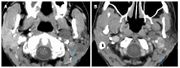

| 21:25, 26 February 2023 | Pineal cavernoma pre surgery 2.jpeg (file) |  |

161 KB | 1 | |

| 17:30, 26 February 2023 | Pineal cavernoma pre surgery 1.jpeg (file) |  |

128 KB | 1 | |

| 17:30, 26 February 2023 | Pineal cavernoma post surgery 1.jpeg (file) |  |

128 KB | 1 | |

| 17:30, 26 February 2023 | Pineal cavernoma pre surgery 2.jpg (file) |  |

853 KB | 1 | |

| 17:29, 26 February 2023 | Pienal cavernoma post surgery 2.jpeg (file) |  |

124 KB | 1 | |